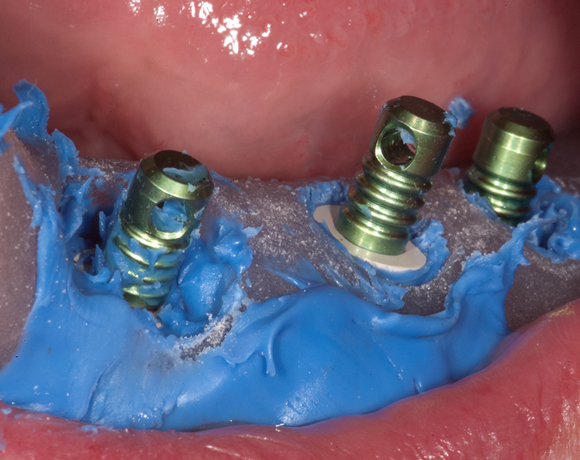

Knochenspaltung Unterkiefer 32 – 36

Die Knochenspaltung auch Bonesplitting genannt, ist eine geeignete Möglichkeit im Unterkieferseitenzahnbereich Knochen aufzubauen, um Implanate setzen zu können. Vorraussetzung ist eine ausreichende Knochenhöhe.

Bei diesem Patientenfall war vor dreizehn Jahren bereits eine Knochenspaltung besprochen

worden, die Patientin hatte allerdings Angst vor dem Eingriff und sich für eine herausnehmbare

Lösung entschieden. Nachdem die endodontisch behandelten Zähne 32 und 33, die mit VMK – Kronen

und Geschiebe versorgt waren, abgebrochen sind, war die Patientin für den Eingriff mit Knochen-

spaltung und drei Implantaten offen. Heute ist sie sehr zufrieden und bereut es nicht gleich diese

Lösung gewählt zu haben.